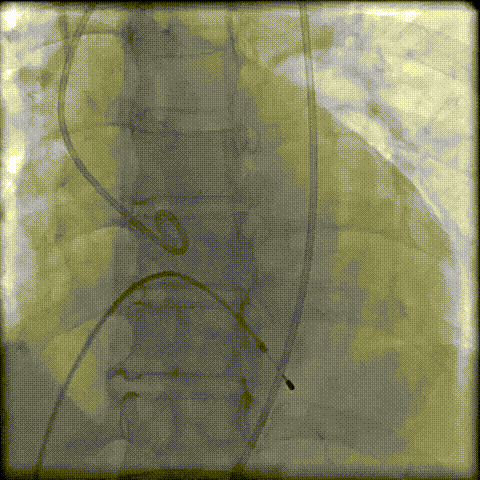

第二次定位释放

顺利脱钩撤鞘,瓣膜位置及形态理想,无明显瓣周漏

术后血流动力学

瓣膜展开良好,无明显瓣周漏;人工瓣膜流速0.97m/s,压差3.73mmHg;植入后30min,EDV 85ml(术前165ml),ESV 36ml(术前67ml)